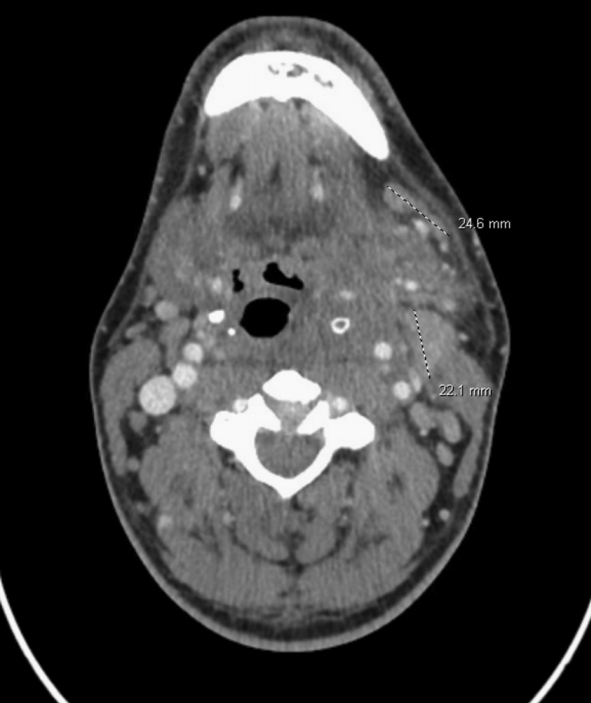

颈部增强CT扫描显示多发龋齿和左侧腭扁桃体肿大,并伴有周围炎性改变(图1)。胸部CT扫描显示双侧多发实性肺结节

图1 颈部CT扫描显示炎性改变延伸至左侧咽旁、咀嚼肌和颈动脉间隙,水肿和脂肪沿左颈部肌筋膜平面延伸,颈阔肌和带状肌不对称增厚。